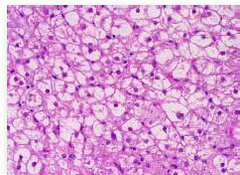

hepatic lipid accumulation

Front

organ? issue?

-Hydropic degeneration of the liver -accentuated lobular pattern; pallor-light pink

Describe this liver